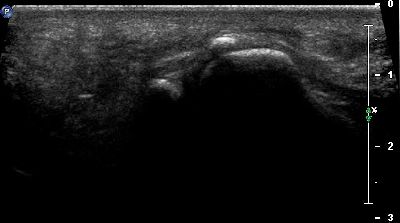

Sesamoidi e Sesamoidi accessori

Alterazioni dei sesamoidi del primo dito Alterazioni sesamoidi primo dito